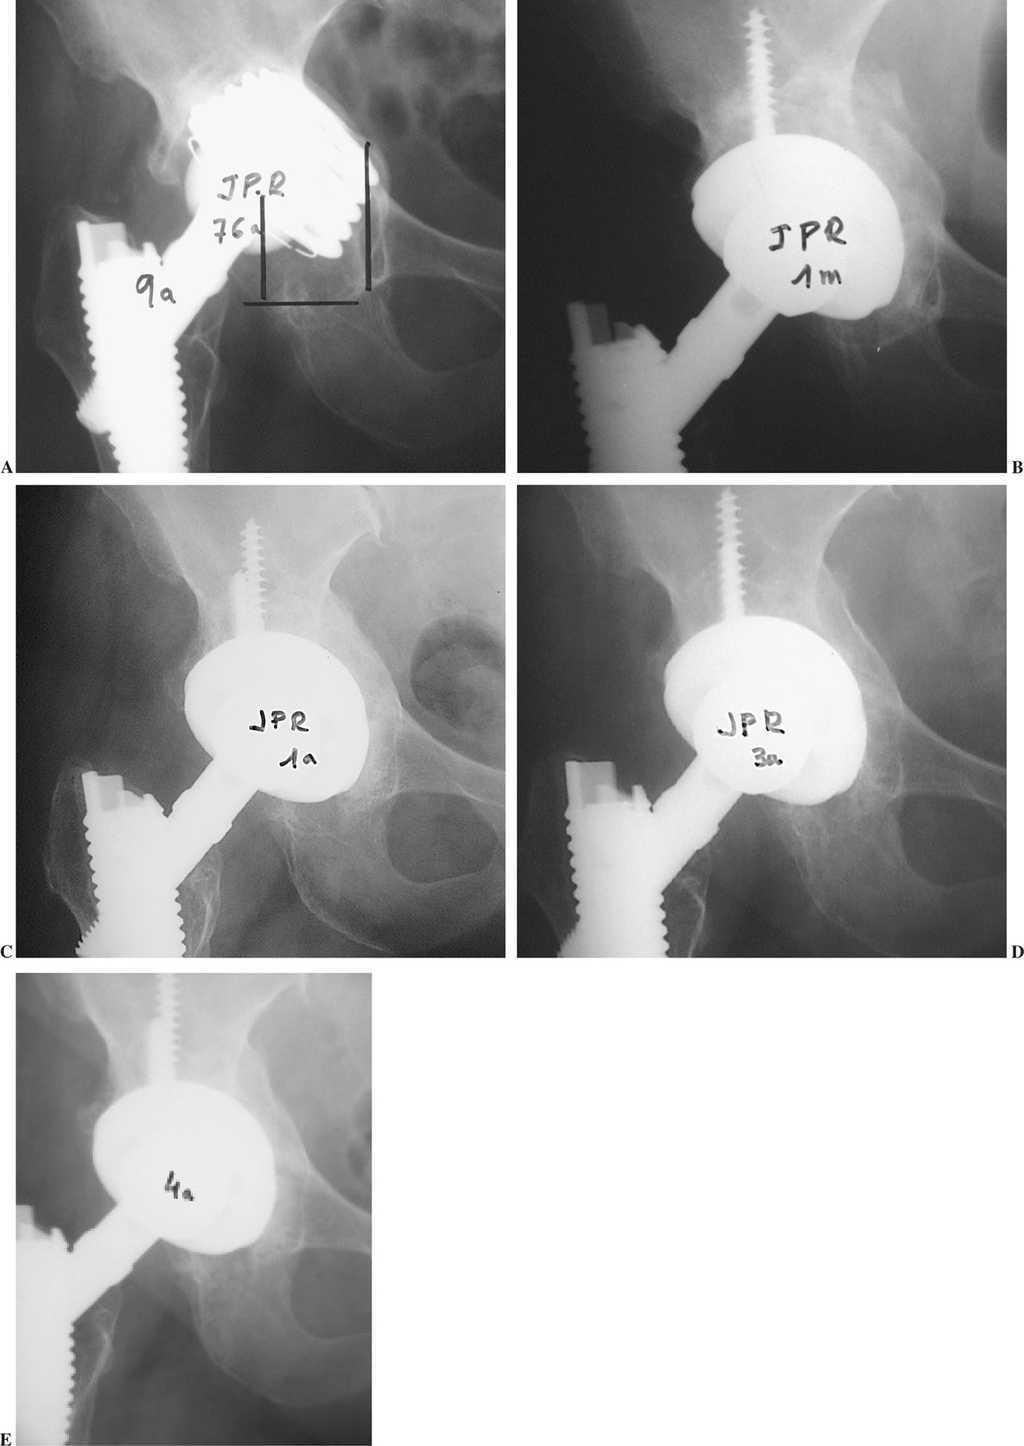

Figura 1.A) Paciente de 76 años con aflojamiento de cotilo de titanio roscado, a los 9 años. Ascenso y medialización del implante; defecto tipo IIIA de Paprosky. B) Cotilo con recubrimiento de hidroxiapatita apoyado en su totalidad sobre injertos óseos de banco fragmentados impactados, al mes de la cirugía. C, D y E) Remodelación progresiva de los injertos a 1, 3 y 4 años, con formación de fondo y techo acetabular de aspecto normal.

Los injertos parecieron integrados con una buena remodelación ósea del techo y reconstrucción de la pared medial en 31 casos (73,8%) (figs. 1 y 2). Hubo reabsorción parcial del injerto en 4 casos (9,5%), con disminución del grosor inicial del injerto o reabsorciones mínimas lacunares. Fue difícil valorar en 7 casos (16,6%) por superposición del implante metálico y el injerto. Los casos de reabsorciones parciales o dificultad de interpretación radiológica no tuvieron traducción clínica.